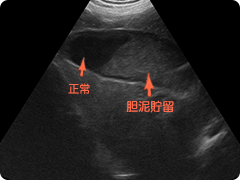

- 胆嚢粘液腫

-

無菌性または細菌性の炎症が胆嚢に生じること、または胆嚢の運動性が障害されること、あるいはその両方が生じることにより胆嚢内の液体が固くなってしまうことで形成しやすくなると考えられています。

胆汁排泄ができなくなって黄疸がみられたり、胆嚢破裂してしまうことがあります。 また、膵炎・副腎皮質機能亢進症・糖尿病・甲状腺機能低下症などによる脂質代謝異常との間にも関連性があるとも考えられています。

嘔吐や腹痛などの症状がある場合や全く症状がなく偶然検査でわかることもあります。超音波検査や肝・胆道系に関わる血液生化学検査や炎症反応をみることで総合的に診断します。

当院では胆嚢炎・甲状腺機能低下症・膵炎等に併発した胆嚢粘液腫が確認されています。内科治療に反応しない場合は胆嚢切除が必要になります。 -

胆泥貯留

正常なさらさらした胆汁は超音波検査では黒く見えます。粘稠度が増すと白っぽく見えてきます。

胆嚢粘液腫

胆嚢内外側が黒く中心部が白くなり、典型的にはキウイフルーツの断面のように見えてきます。

切除した胆嚢

病理組織学的検査で胆嚢粘液腫と診断されました。